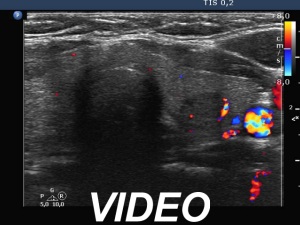

Ultrasonography. The thyroid was echonormal. There was a discrete, deeply hypoechoic area in the dorsal part of the right lobe. Although the dimensions were only 4x7x5 mm, width, depth, length, respectively, the lesion would correspond to a TIRADS 5 lesion because it was very hypoechoic and presented with irregular shape. However, color Doppler mode proved that this was indeed a vessel and not a solid thyroid tissue. The left lobe had a minimally hypoechoic lesion which largest diameter was 9 mm.

Comments. Although some vascular patterns significantly increase the risk of malignancy, none of the TIRADS include vascularity among suspicious characteristics. The reason for this is the lack of standardization and the poor sensitivity and specificity. On the other hand, we must investigate the thyroid with color Doppler mode because we never know when to gain significant advantage of the technique. This case study is one of the many examples.